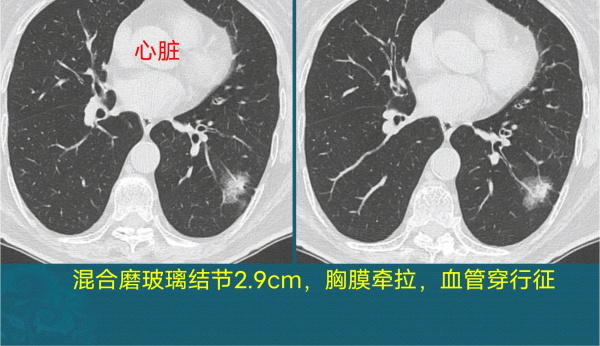

这位病人是个混合磨玻璃结节,恶性征象比较多,有分叶征、血管穿行征、胸膜牵拉,并且内部白色实性成分与磨玻璃区分界不清晰。

另外大家看它的血管穿行,当白色树枝状血管进入结节内部后,变得增粗、僵直、部分边缘模糊。

他后来做了微创手术,病理是浸润性肺腺癌。